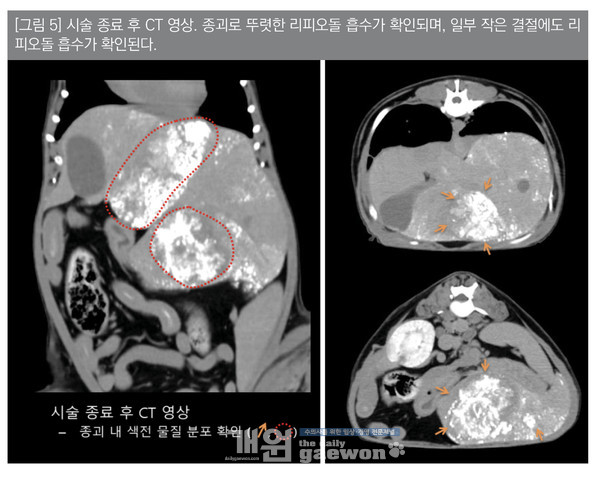

시술 후 CT 촬영을 통해 간 종괴로 뚜렷한 리피오돌 흡수를 다시 한번 확인하였다[그림 5]. 환자는 시술 직후 마취에서 회복하였으며, 시술 4시간 후 당일 퇴원하였다.시술 후 시술과 관련한 부작용은 확인되지 않았다.